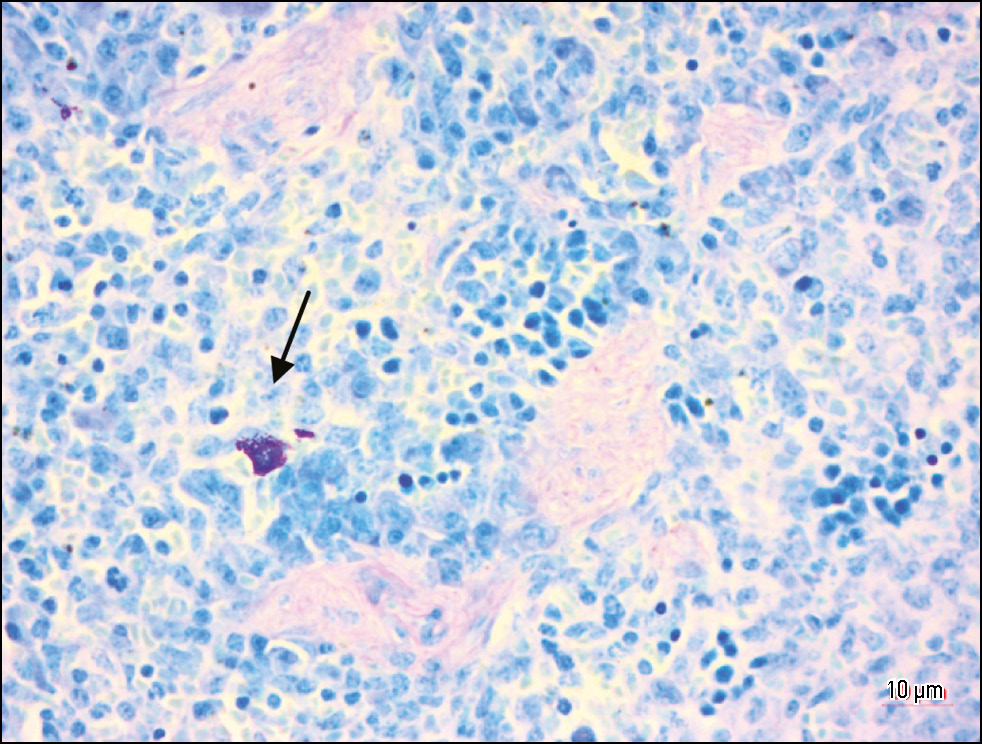

METHODS: An experimental, single-center, prospective, controlled study was conducted. Spleen samples from laboratory mice (n = 23) were assessed. The population of mast cells was quantitatively assessed on histological sections of the spleen. The mice were divided into 5 groups: Group 1 included intact animals (n = 3); Group 2 included irradiated animals with a total absorbed dose of 7 Gy (n = 5); Group 3 included irradiated animals with a total absorbed dose of 7 Gy who received oral soluble beta-D-glucan 15 minutes before irradiation (n = 5); Group 4 included irradiated animals with a total absorbed dose of 18 Gy (n = 5); Group 5 included irradiated animals with a total absorbed dose of 18 Gy who received oral soluble beta-D-glucan 15 minutes before irradiation (n = 5). Samples were collected on days 14 and 30 after the start of experimental exposure. Samples were fixed in 10% buffered formalin, dehydrated in alcohol, and embedded in paraffin. The Romanowsky–Giemsa staining was used. The structure and number of mast cells were assessed on each histological slide. Statistical analysis of the findings was performed.

RESULTS: The density of mast cells in the spleen of laboratory mice at an absorbed dose of 7 Gy changed insignificantly compared to the intact group. At a total absorbed dose of 18 Gy, there was a significant increase in the density and functional activity of mast cells. Beta-D-glucan administration before irradiation at a total absorbed dose of 7 Gy and 18 Gy reduced the number of mast cells by 2.5 times and 1.25 times, respectively, compared to irradiated animals without beta-D-glucan administration (Group 4).

CONCLUSION: The density of mast cells in the spleen depends on the absorbed dose of X-ray irradiation. Beta-D-glucan administration 15 minutes before exposure reduces the density of mast cells, which can be considered a positive radioprotective effect.